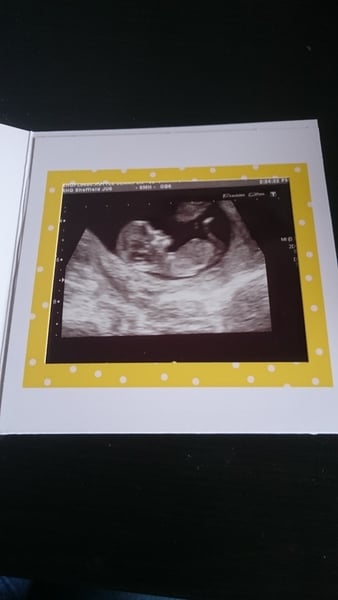

Here's my scan photo from earlier today ....

Biscuits, official scans & the end of the trimester - Later November due dates this way...